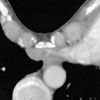

Figure 3 – This CT scan of the chest shows leftward displacement of the

heart-a sequela of pectus excavatum.

Pectus excavatum, also referred to as funnel chest or funnel breast, is the most common anterior chest wall deformity observed in children (incidence, 8 in 1000).1,2 This skeletal abnormality results from an overgrowth of the length of rib cartilages 4 through 8, which prevents sternum elevation at birth.2 Sequelae include leftward displacement of the heart (Figure 3) and alterations of ventilation with mild restriction.3